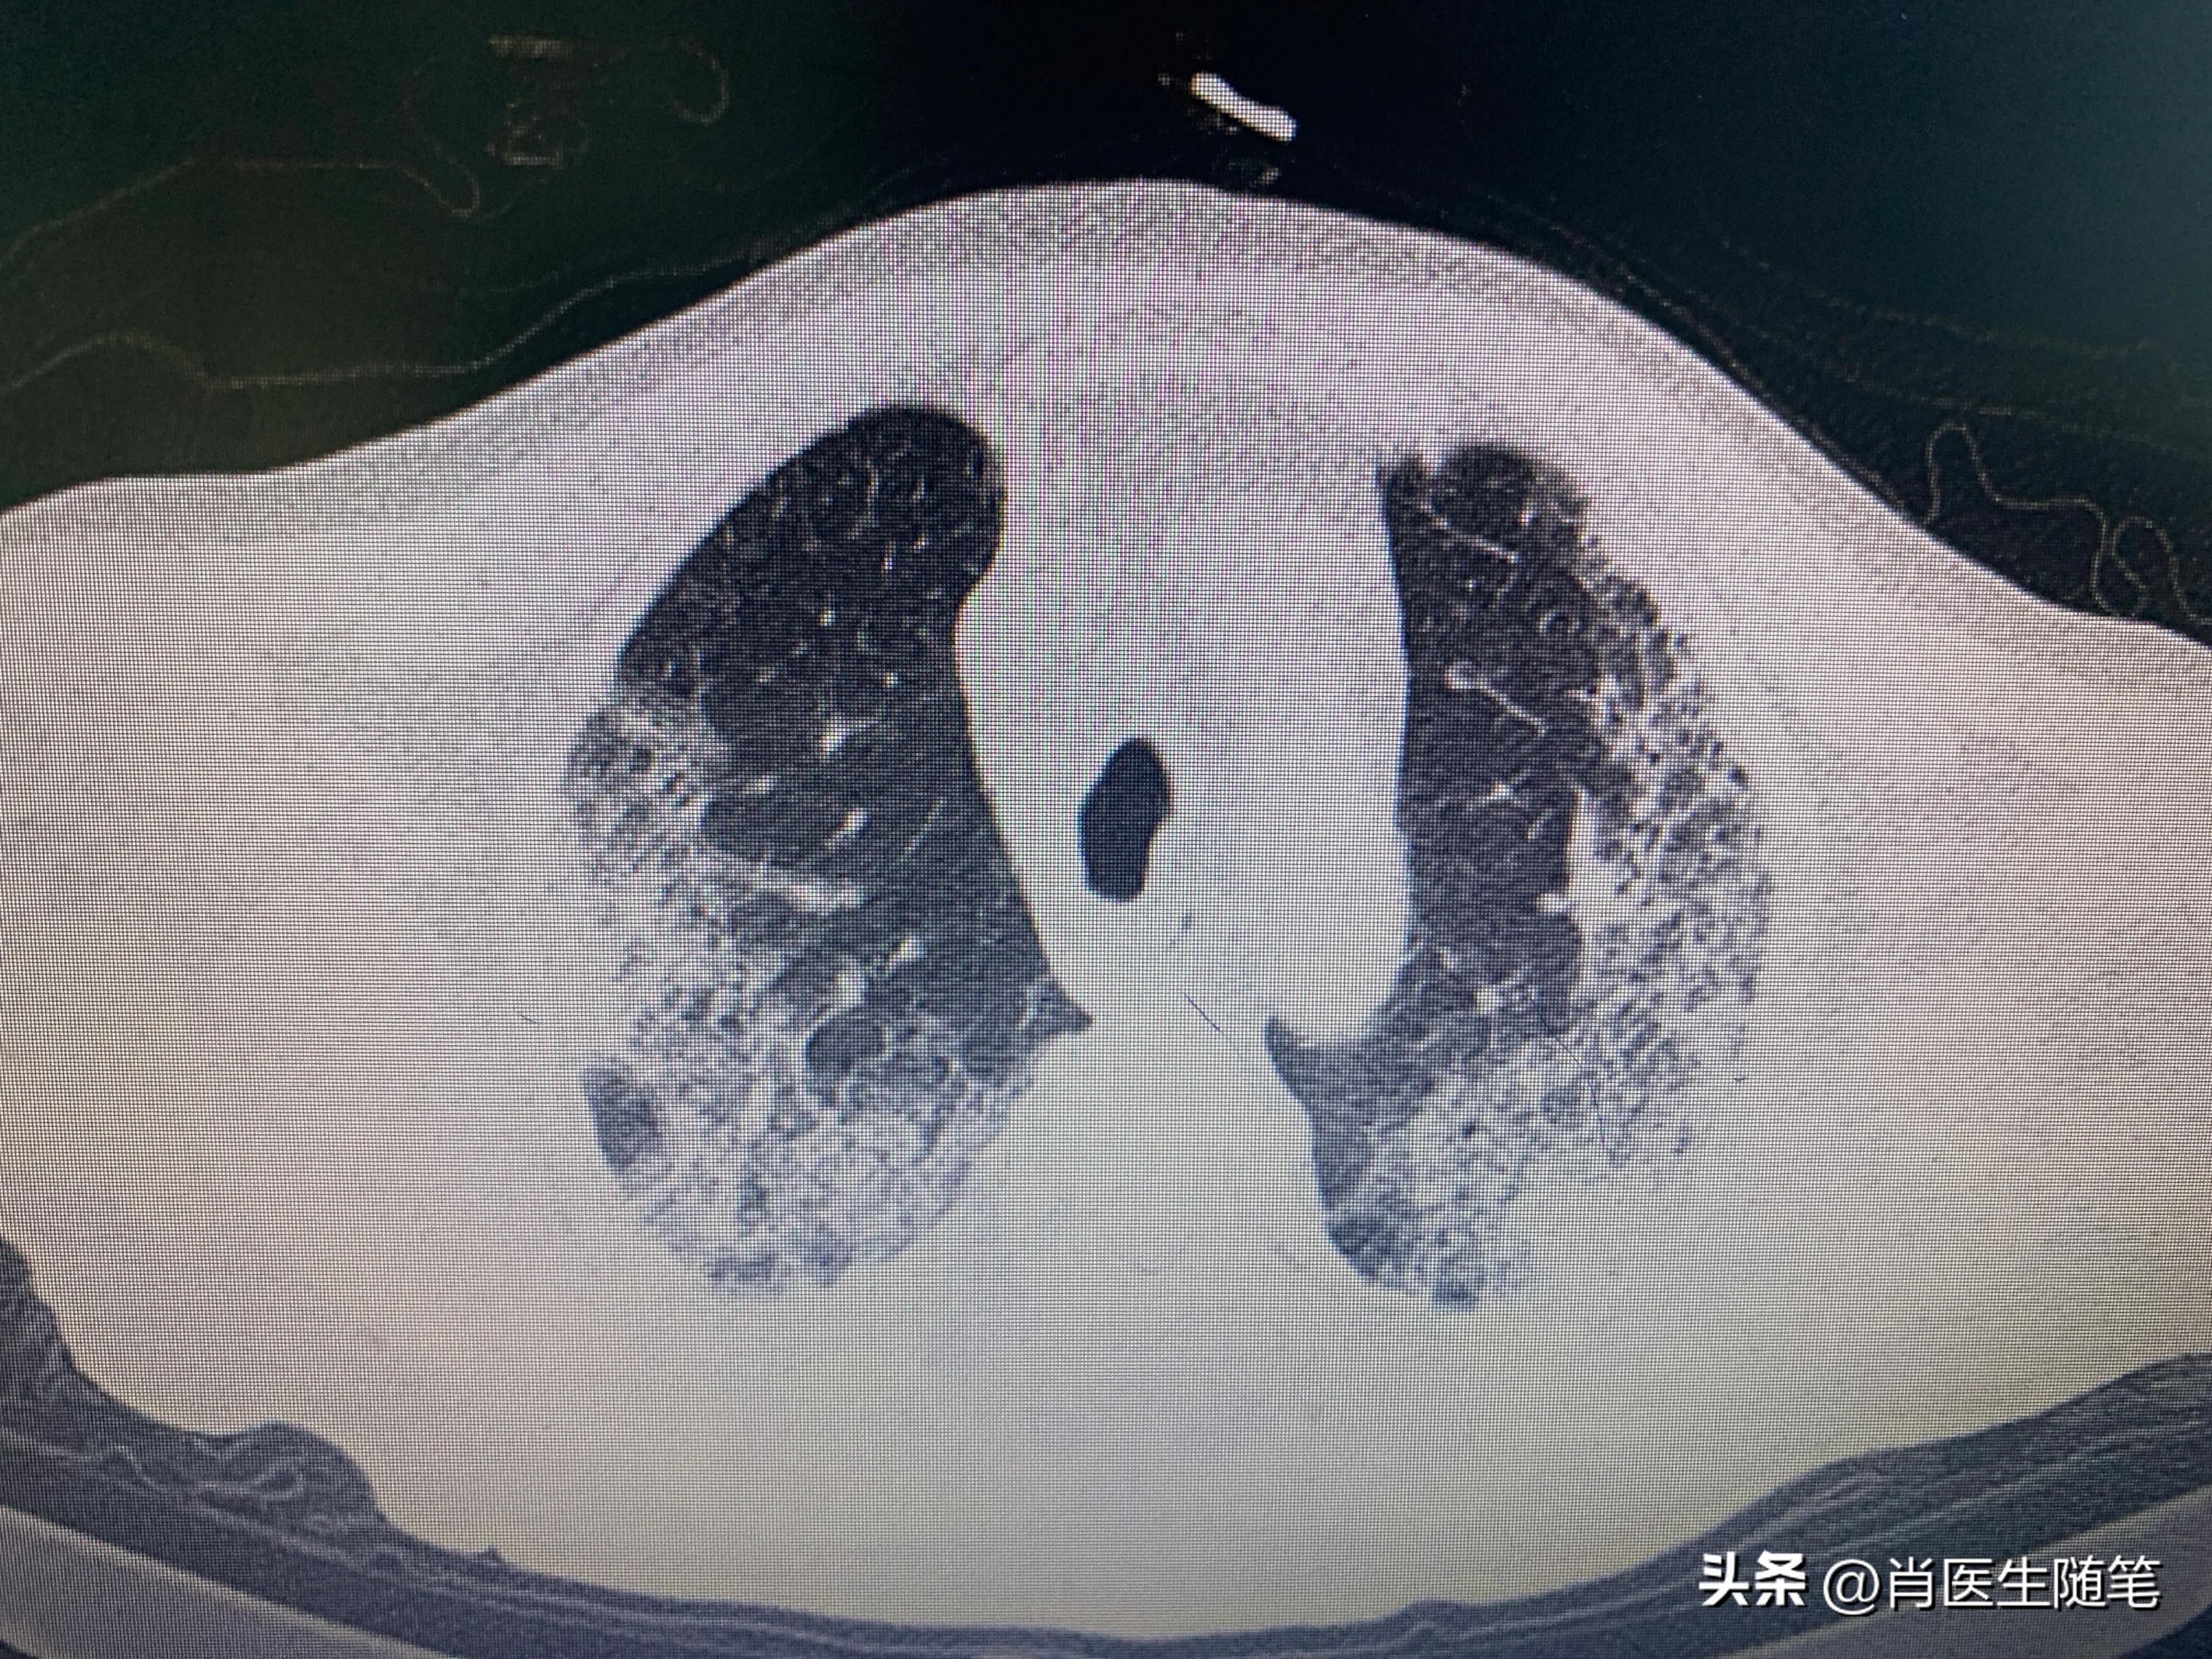

入院后2023-01-13胸部CT提示双肺炎症,纵膈多发淋巴结显示,部分钙化,双侧胸腔积液,心包积液。血提示炎症指标升高,白蛋白略低,33g/l。血氧饱和度吸氧下95%。